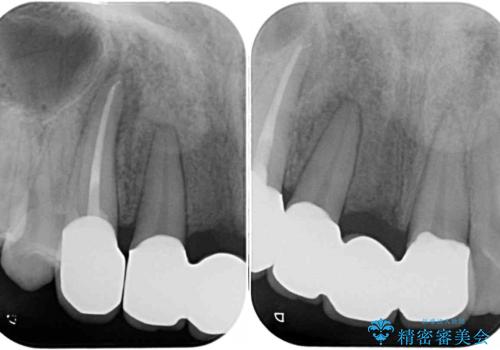

補助装置により上顎歯列を遠心移動させたため、非抜歯でしたが口元の突出感をある程度改善させることができました。

欠けてしまった前歯もオールセラミッククラウンにて自然に補綴することができました。